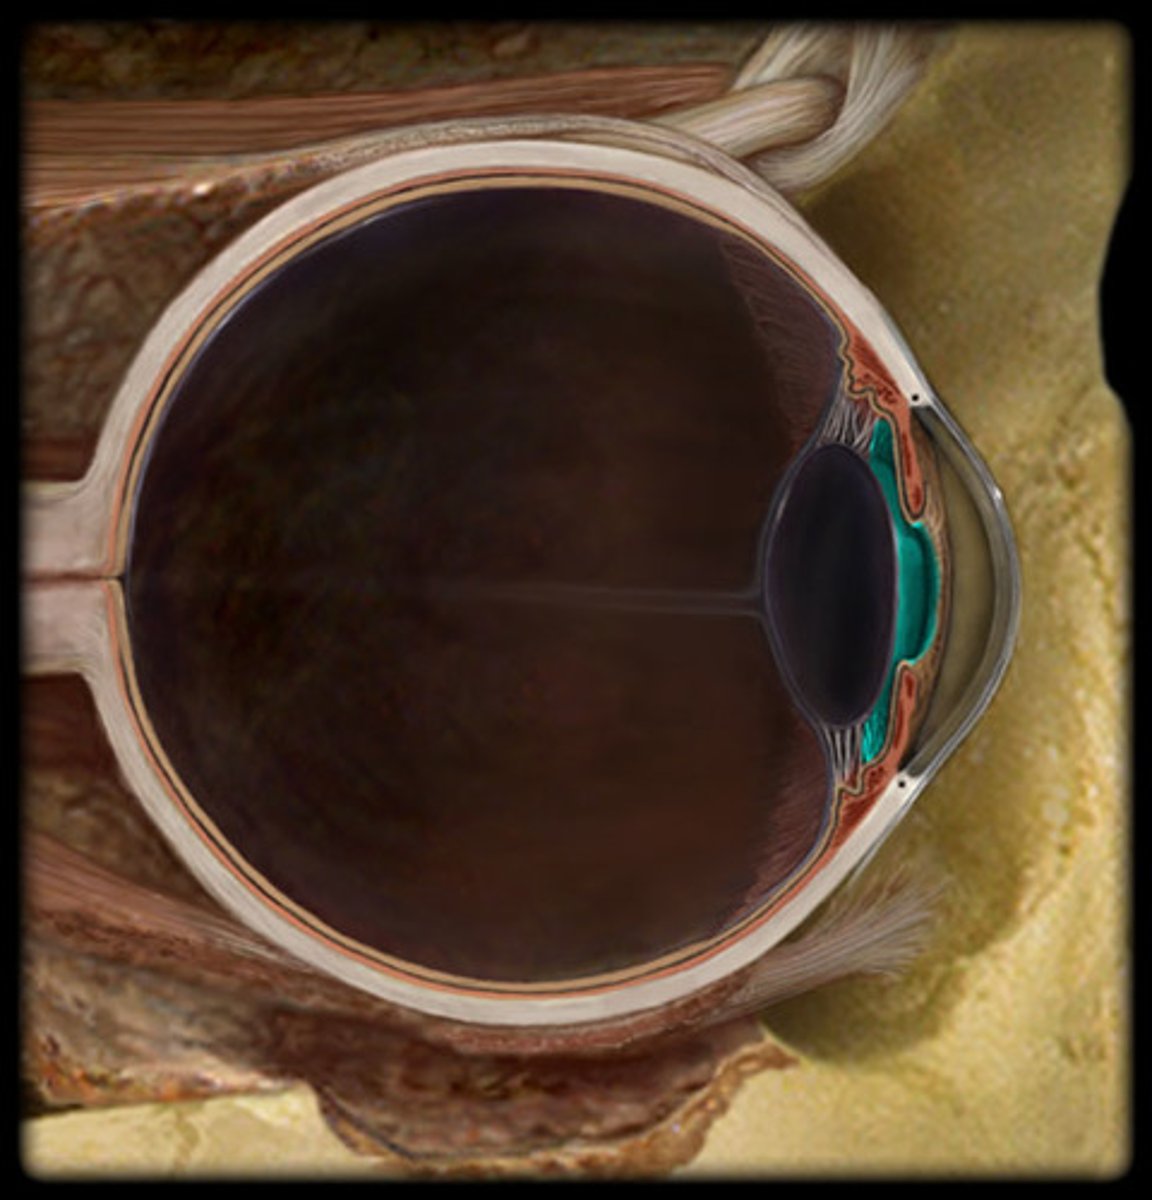

Eye

anterior chamber

posterior chamber

choroid

ciliary body

cornea

iris

lens

pupil

Sclera

suspensory ligament of eye

optic nerve

Retina